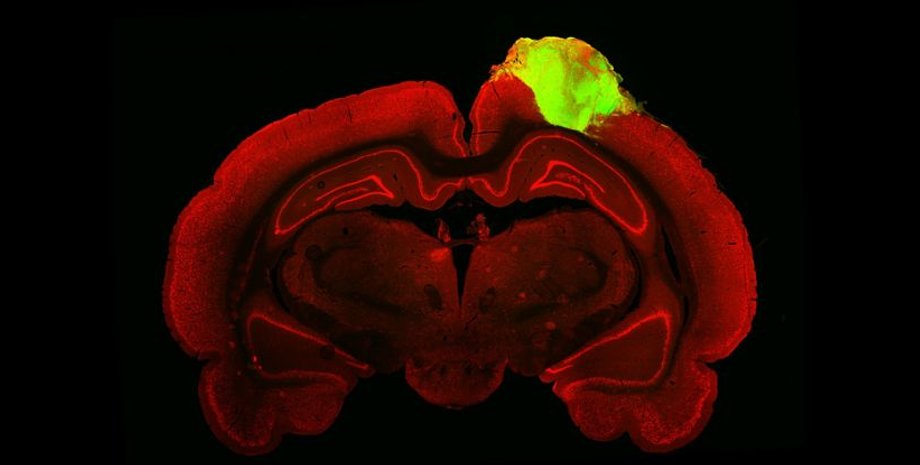

Фото: Jgamadze et al., Cell Stem Cell

Щоб виростити людський "мінімозок", дослідники використовували індуковані стовбурові плюрипотентні клітини, генетично модифіковані для експресії зеленого флуоресцентного білка. Індуковані стовбурові клітини генеруються з дорослих стовбурових клітин, реконструйованих у недиференційований стан, подібний до ембріонального; тобто вони можуть розвиватися в безліч різних типів клітин. Зелений флуоресцентний білок надає органоїдам здатності флуоресціювати.

Ці стовбурові клітини були вирощені в нейрони людини протягом приблизно 80 днів, перетворившись на невеликі органоїди. Після того, як органоїди були вирощені, дослідники приступили до їхньої пересадки в мозок 10 дорослих самців щурів.